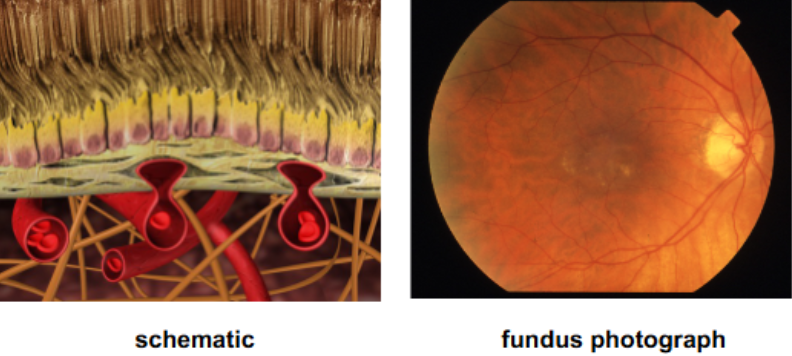

RPE cells age & accumulate residual bodies with lipofuscin

decreased RPE function & changes in permeability of Bruch’s membrane may lead to drusen

drusen may initiate inflammatory cascade that can contribute to AMD progression

disrupt RPE function

loss of RPE & PRs

dysfunction in Bruch’s

VEGF

CNVM

describe the pathogenesis of AMD

characterized by deep yellow deposits called drusen, RPE pigmentation changes, & atrophy

multilpe, discrete, round, slightly elevated, variable sized, yellow/white sub-RPE deposits in the macula & posterior pole b/t the RPE & Bruch’s membrane

bilateral

clustered in macular or paramacular area

tend to increase in # & size but can fade from view & decrease in number

change in size/shape/distribution/color/consistency w/ time